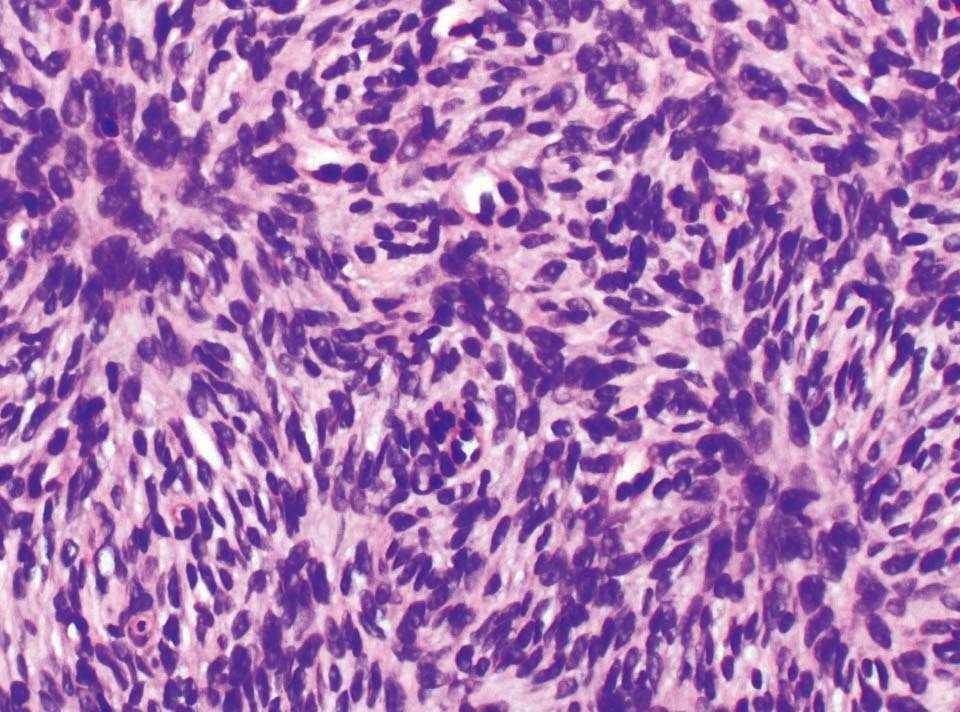

Figura 4. Las células fusiformes del infiltrado se disponen en fascículos cortos adoptando un patrón arremolinado. (Hematoxilina-eosina, ×200.)

El diagnóstico del DFSP es histológico7, 8. Se trata de un tumor de células fusiformes de núcleo alargado que se disponen en fascículos cortos adoptando un patrón estoriforme o arremolinado característico. Las células muestran una atipia celular mínima y pocas mitosis. Tiene un patrón de crecimiento infiltrativo y generalmente se extiende hasta la dermis profunda y el tejido celular subcutáneo. El tumor de Bednar es una variante histológica del DFSP, que tiene células dendríticas que contienen melanina entre las células fusiformes9. Otro subtipo es el mixoide, con áreas de mucina intersticial entre las células fusiformes10. En la inmunohistoquímica es muy importante destacar la positividad de las células del tumor con el anticuerpo para CD34. El CD34 es un antígeno de superficie que se expresa en las células madre hematopoyéticas, en el endotelio y en la piel (alrededor de las estructuras foliculares, glándulas sebáceas y sudoríparas). Este antígeno puede estar presente también en neoplasias como ocurre en el DFSP y es de gran ayuda para diferenciarlo de otros tumores fibrohistiocitarios. La tenascina es un marcador estromal de tejido conectivo que suele ser positivo en las células del DFSP y es característico que la positividad se extienda hacia el tejido celular subcutáneo. Vimentina también es positiva y el resto de marcadores (factor XIIIa, S-100, actina y desmina) son negativos. Citogenéticamente, el DFSP se caracteriza por presentar la translocación recíproca t(17;22)(q22;q13) que condiciona en la fusión del gen del colágeno tipo 1 (COL1A1), en el cromosoma 17q, con el gen de la cadena beta del factor de crecimiento derivado de las plaquetas (PDGFB), en el cromosoma 22q1, 3 11.